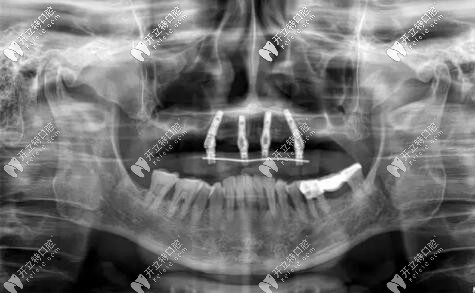

半口種植牙前

西安美奧牙科all-on-6種植牙案例

修復(fù)前

病史上頜于10年前因牙周病導(dǎo)致的牙齒缺失,曾做過可摘戴活動(dòng)義齒修復(fù)。

惠先生種植方案:前期ALL-ON-4即刻負(fù)重,后期上頜竇外提升,同期植入兩顆種植體,做ALL-ON-6,馬龍一體橋。